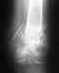

Перелом левой пяточной кости со смещением!!!

Здравствуйте!Меня зовут Михаил. Мне 23 года, рост 175 см, вес 75 кг. 17.11.2009 упал с высоты, попал в больницу с диагнозом перелом левой пяточной кости со смещением. Была большая опухоль в области лодыжки, спустя 2 недели опухоль прошла и наложили гипс до колена под углом 90 градусов между голенью и стопой. 11.02.2010 сняли гипс. Из за некомпетентности местных врачей поехал в нижегородский институт травматологии и ортопедии. Назначали ЛФК, кроссовки, ступинаторы.ЛФК начал заниматься последние 4 дня, жалуюсь на значительные боли, до сих пор передвигаюсь с помощью костылей при попытки наступание на носок острая боль в области архилесого сухожилия, при попытки наступание на ступню острая боль в области пятки. Снимки прилагаются + сегодняшние фотографии ноги.Требуется квалифицированная помощь. И возникает вопрос буду ли я годен в армию. переживаю за неправильную геометрию с задней стороны ноги.снимки 17.11.2009 до гипсаhttp://s45.radikal.ru/i109/1003/2d/bb1a2d28eb0a.jpghttp://s39.radikal.ru/i085/1003/51/8ec7a702f6c7.jpgснимки 03.03.2010 после гипсаhttp://i015.radikal.ru/1003/92/9f229ea760c2.jpghttp://s58.radikal.ru/i162/1003/f8/1957b396bb06.jpgфотографии ноги на сегодняшний деньhttp://s19.radikal.ru/i192/1003/29/58efe0c3bf4b.jpghttp://s001.radikal.ru/i194/1003/bf/ba87e1b68004.jpghttp://i074.radikal.ru/1003/ff/503ccdce2995.jpghttp://s58.radikal.ru/i159/1003/9a/8000b52fa132.jpgЗаранее благодарен.